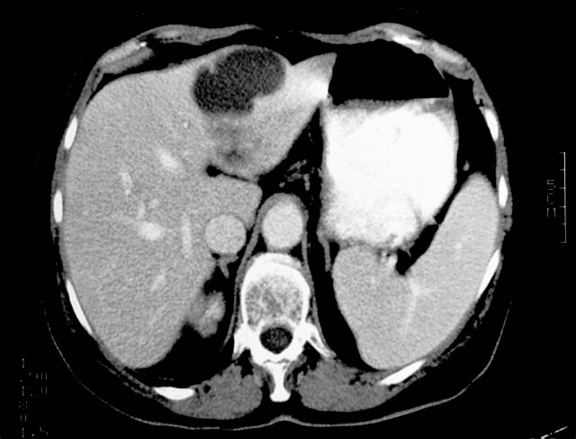

When you see a large mass in the abdomen that you don’t know where it is arising from